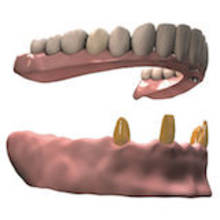

Modellgußprothese: nicht schön aber stabil und günstig

Stahlkronen, Modellgußprothese: als günstiges, verlässliches Material für Zahnersatz gibt es zurzeit keine Alternativen zum NEM. Modellguss-Legierungen bestehen hauptsächlich aus Kobalt (Co) ca. 60% Chrom (Cr) ca. 30% und Molybdän (Mo) ca. 5%. Sie ist nickelfrei und löst entgegen vieler Befürchtungen nur selten Allergien aus. NEM für Kronen/Brücken enthält zusätzlich noch ca. 5% Wolfram (W) auf Kosten des Chromanteils.

Herausnehmbare Prothesen: Kunststoff als Material für Zahnersatz

Bei herausnehmbarem Zahnersatz kann man auf einen Prothesenkunststoff eigentlich nie verzichten.

• zahngetragene Teilprothesen (z.B. Teleskopprothesen, Interimsprothesen, Klammerprothesen)

• implantatgetragene Prothesen (z.B.Stegprothesen, Locator®-Prothesen)